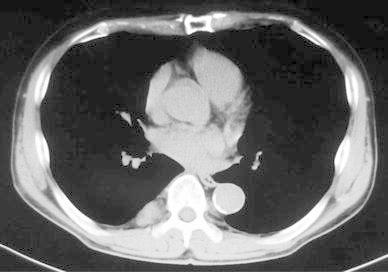

Fig. 2.

Chest CT shows a tumor located in the right posterior mediastinum. It is 2.5 cm in diameter beside the T8 and T9 thoracic vertebrae